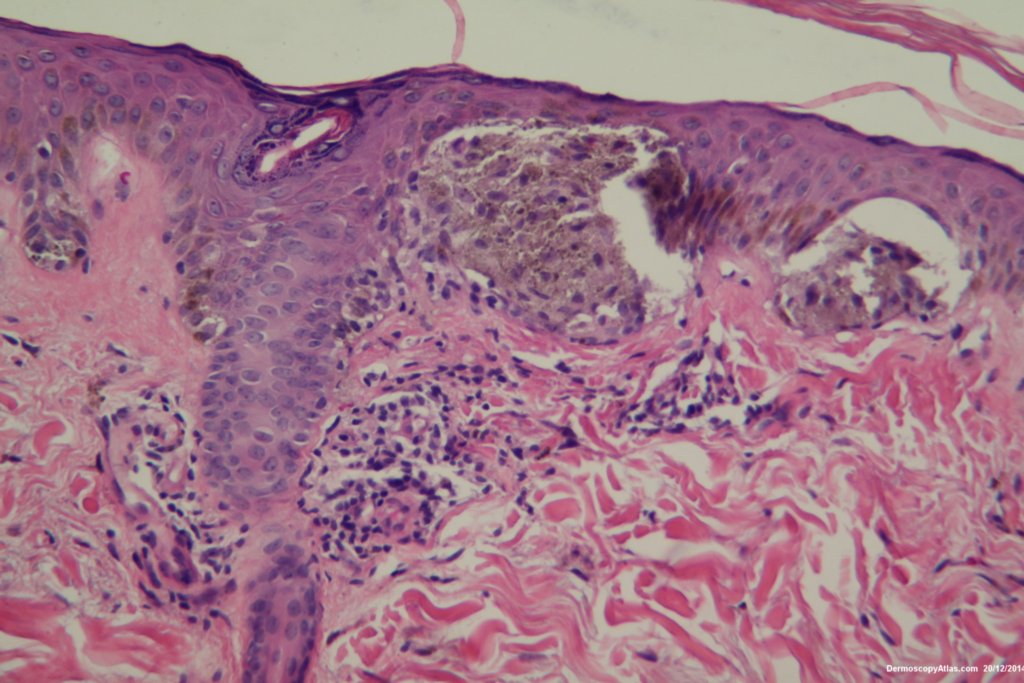

The dermatoscopy shows dark clods of varying sizes both peripheral and central. These represent nests of rapidly growing melanocytes. The lesion is dark because the nests press high into the epidermis giving a black colour. Sometimes cells are extruded into the stratum corneum exagerating the dark colour.

The histopathology shows nests of epitheliod and spindled cells with lots of melanin in them. There are a few melanophages in the dermis. There is no inflammatory reaction beneath this lesion. There were no mitoses. This is just a junctional lesion ie no nests of cells in the dermis.